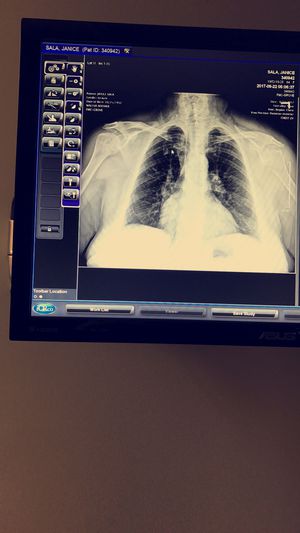

Mass

2.5cm right lower lobe mass